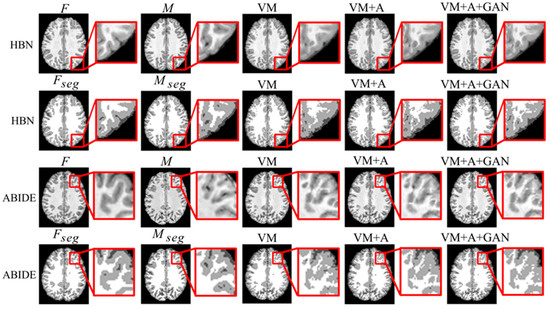

Second, the proposed GAN method is compared with the VM and VM + A methods. Figure 4 shows the registered moving image and the fixed image. Moreover, the first row represents the original image from the HBN dataset, and the second row represents the segmentation image corresponding to the original image from the HBN dataset. Similarly, the third row represents the original image from the ABIDE dataset, and the fourth row represents the segmentation image corresponding to the original image from the ABIDE dataset. Additionally, the enlarged figure on the right shows that the result for the proposed method regarding the training of the registration, augmented, and discrimination networks together is closer to the fixed image. Through the experimental results, the performance of the registration, augmented, and discrimination networks when trained together is verifiably better than that of the registration network trained individually and of the registration and augmented networks trained simultaneously.

Figure 4. Registration results based on deep learning methods. Among them, VM represents the result obtained by the VoxelMorph method, VM + A represents the result obtained by training the registration network and the enhanced network together, and VM + A + GAN represents the result obtained by our method.